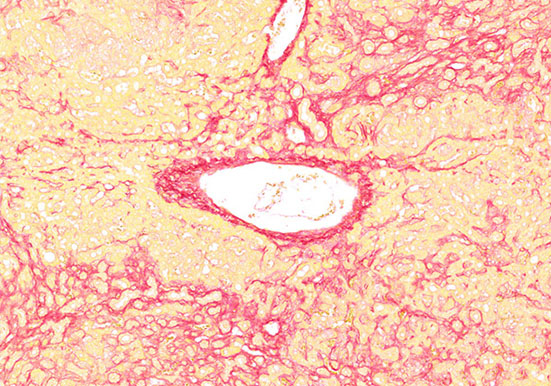

Masson染色

Masson染色丽春红酸性品红-苯胺蓝染色,是用于检测动物组织中胶原纤维的一种染色方法之一,能够将胶原纤维染成蓝色,肌纤维、和红细胞呈红色,可用于鉴胶原纤维和肌纤维;并···

天狼星红染色

技术原理天狼猩红和KWS都是强酸性染料,易与胶原分子中的碱性基团结合,吸附牢固。偏振光镜检查,胶原纤维有正的单轴双折射光的属性,与KWS-天狼猩红结合,可增强双折射,提···